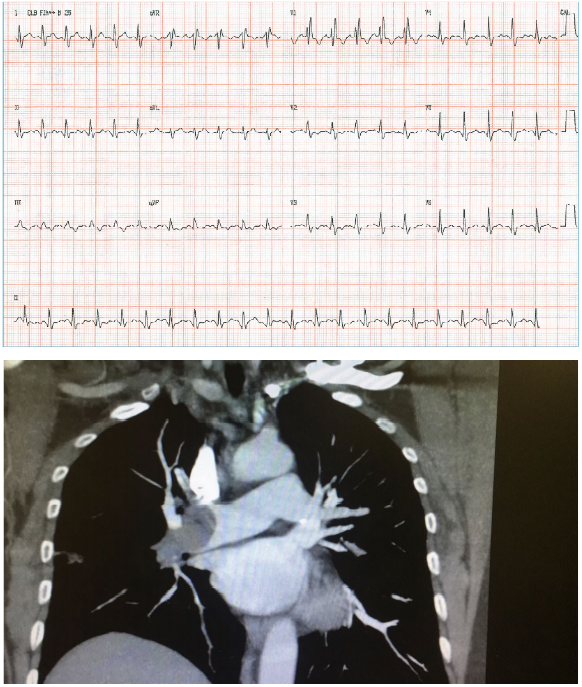

Sr. JG, 60 anos, procura o serviço hospitalar com falta de ar e dor torácica iniciada há 40 minutos. Referiu que, na

véspera, começou a se sentir mal e esteve no mesmo hospital, quando foi examinado e realizou radiografia de tórax

e eletrocardiograma. Na ocasião, os médicos lhe disseram que não encontraram anormalidades relevantes e deram

alta a ele, que foi para casa. O paciente possui histórico de tabagismo crônico. Exame físico: FC = 134 bpm, FR+

36irpm, PA = 89x58 mmHg, Oximetria = 85%, sudorético. AR = murmúrio vesicular fisiológico, sem ruídos

adventícios; ACV: bulhas rítmicas e fonéticas. Seguem abaixo as imagens do ECG e TC de tórax.

Qual a conduta CORRETA para esse paciente?

Qual a conduta CORRETA para esse paciente?